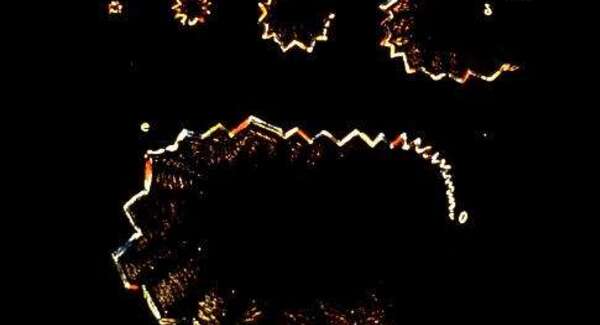

Un peu de "self-neurology" : l'aura visuelle

La « self-neurology » consiste à pratiquer la neurologie sur soi-même . Oliver Sacks en était un habile coutumier, mais dans les publications...